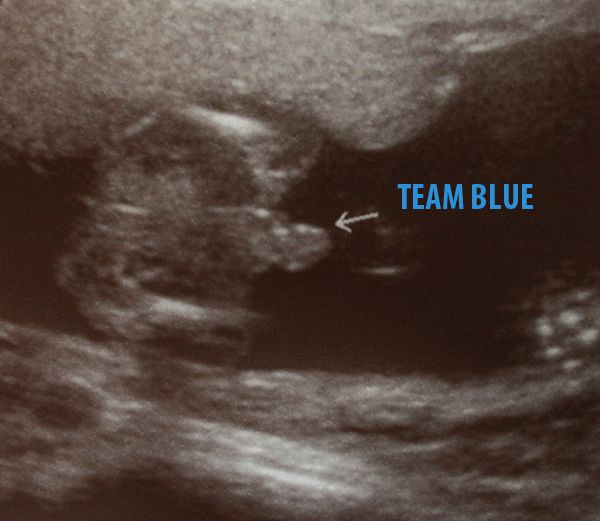

Our Little Hercules, has been confirmed 100% boy at his 20 week ultrasound =)